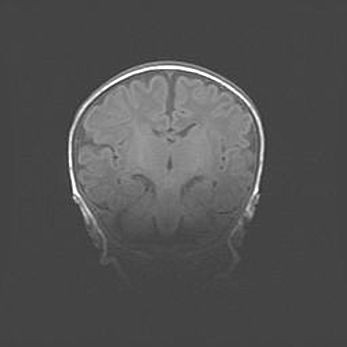

Неполная лизэнцефалия (пахигирия). Открытая гидроцефалия.

Возраст: 17 дней

Вес: 3110 г

Пол: мужской

Окружность головы: 33,5 см

Срок гестации: 35-36 недель

Лизэнцефалия—недоразвитие корковой пластинки и мозговых извилин в результате нарушения миграции нейронов коры. Поверхность мозговых полушарий гладкая. Микроскопически выявляется отсутствие нормальных слоев коры и скопление групп нейронов в подкорковом белом веществе.

Пахигирия—уменьшение числа вторичных извилин. В пораженном полушарии нервные клетки образуют толстый недифференцированный слой с неправильно расположенными нервными волокнами и группами гетеротопных клеток. Нервные клетки незрелые. Белое вещество истончено. При этом нередко аномально развит корково-спинномозговой путь.